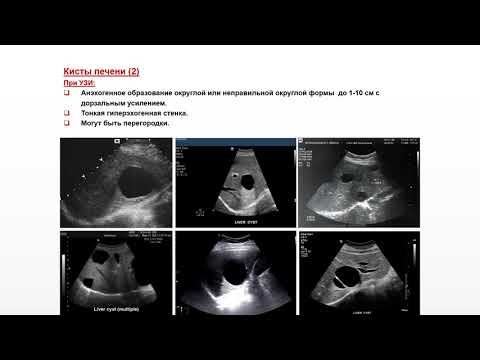

Ультразвуковая диагностика (УЗИ). Доктор Иогансен. Выпуск 10. Диффузные изменения печени. Часть 2.